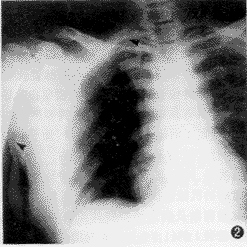

【摘要】 目的 比较在X线辅助下经外周静脉至中心静脉置管 (peripherally inserted central catheter, PICC) 与传统的经锁骨下静脉至中心静脉置管(central venous catheter, CVC)两种方法的优越性及并发症。方法 自1997年1月至1998年12月期间,在X线监视下,对PICC和CVC各60例病人进行临床研究,观察指标包括置管成功率、导管尖端的位置、并发症发生率。两组结果经显著性检验比较。 结果 经X线影像证实,PICC与CVC组一次穿刺置管成功率分别为95.0%(57/60例)和88.3%(53/60例),t=1.745, P=0.19;置管时间平均分别为13天(6~98 天)和14天(7~104 天) ,F=0.049, P=0.83;导管总阻塞率分别为6.7%(4/60例)和5.0%(3/60例),t=0.152, P=0.70;其中PICC组3Fr 型导管(20 G穿刺针)阻塞率(3/20例, 15.0%)高于4Fr 型导管(18 G穿刺针)(1/20例, 5.0%),t=1.111, P=0.29;导管尖端异位率分别为5.0% (3 /60例)和6.7%(4/60例),t=0.152, P=0.70,但PICC组经调整导管位置,并经X线影像证实,导管尖端均到达理想预定部位而继续使用;而CVC组异位导管均予以拔除。PICC组导管接头破裂1例(1.7%);外周静脉炎发生率为5.0%(3/60例) ......